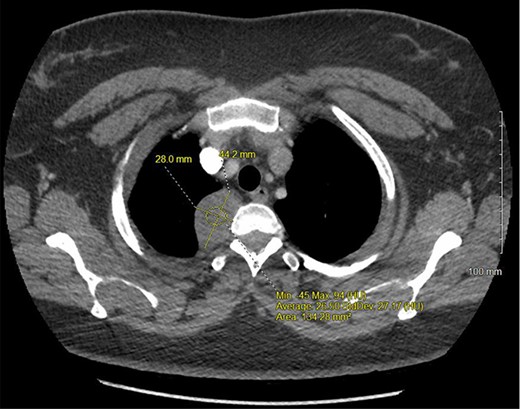

A 36-year-old female presented to an outside emergency department reporting chest pain, dizziness and abdominal pain for 7 hours. A computed tomography (CT) angiogram of the chest revealed a right paraspinal 4.2 × 2.8 × 3.3-cm cystic mass at the level of T2-3, which was well-circumscribed (Figs 1 and 2).

CT chest with IV contrast transverse view with detailed measurements of right T2-T3 paravertebral mass.